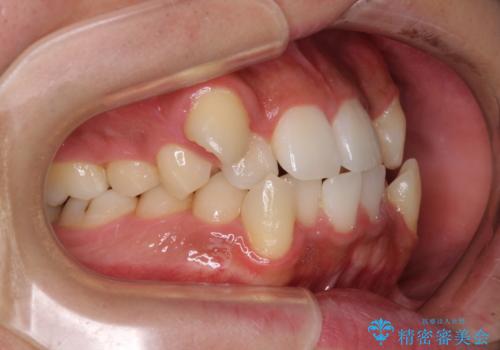

上下の八重歯とクロスバイト ワイヤー装置での抜歯矯正

- 八重歯とクロスバイトを気にして来院された患者様です。

上下ともに八重歯が顕著であり、前歯のクロスバイトがあったため、上下左右の第一小臼歯4本を抜歯し、ワイヤー装置での抜歯矯正を行うこととしました。